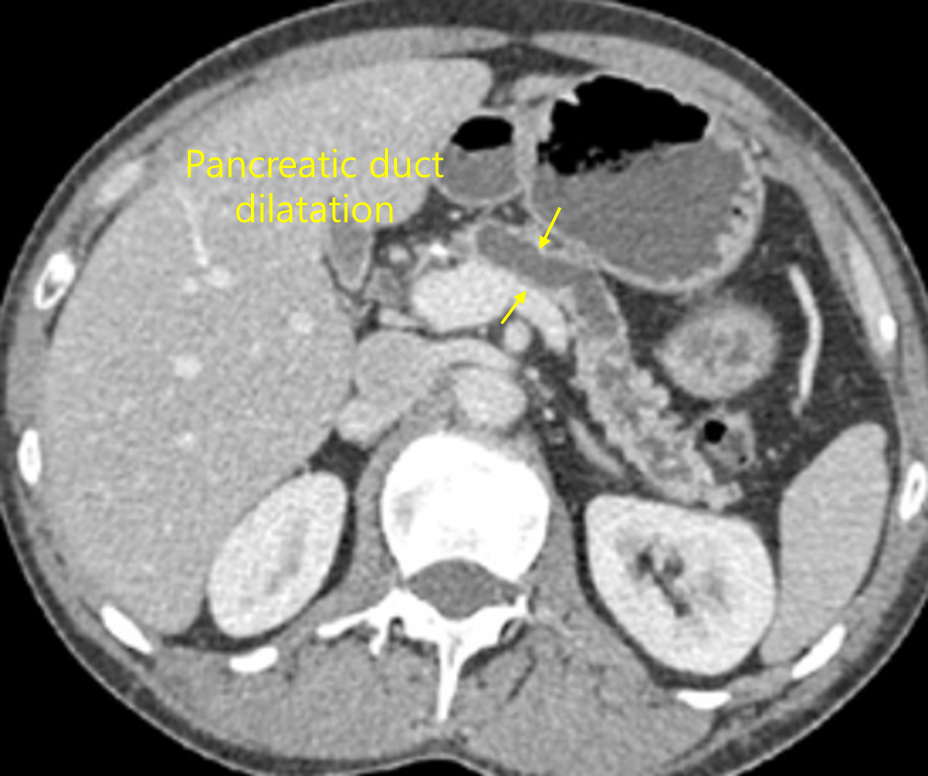

55세 남자가 3개월 전부터 윗배가 아파서 병원에 왔다. 당뇨병으로 치료 중이고 20년간 거의 매일 소주 1병씩 마셨으며 30갑·년의 흡연자이다. 혈압 135/90mmHg, 맥박 70회/분, 호흡 18회/분, 체온 36.3℃이다. 배는 편평하고 장음은 정상이다. 압통이나 반동압통은 없다. 혈액검사 결과는 다음과 같다. 복부 컴퓨터단층촬영 사진이다. 진단은?

백혈구 8,200/mm3, 혈색소 11.3g/dL, 혈소판 165,000/mm3, 아스파르테이트아미노전달효소 92U/L, 알라닌아미노전달효소 60U/L, 알칼리인산분해효소 125U/L, 감마글루타밀전달효소 220U/L, 아밀라아제 110U/L, 리파제 18U/L, HBsAg(+), anti-HBs(-), anti-HCV(-), HBV DNA(-), 암항원(CA) 19-9 32U/mL(참고치, <37), 알파태아단백질 5.2ng/mL(참고치, <8.5)

Img | CT: 췌관의 불규칙한 확장 |

만성적인 상복부 통증, 당뇨, 음주력, 흡연력으로부터 만성 췌장염을 의심할 수 있고, CT 상 췌관 확장 소견도 만성 췌장염의 진단에 도움이 된다.